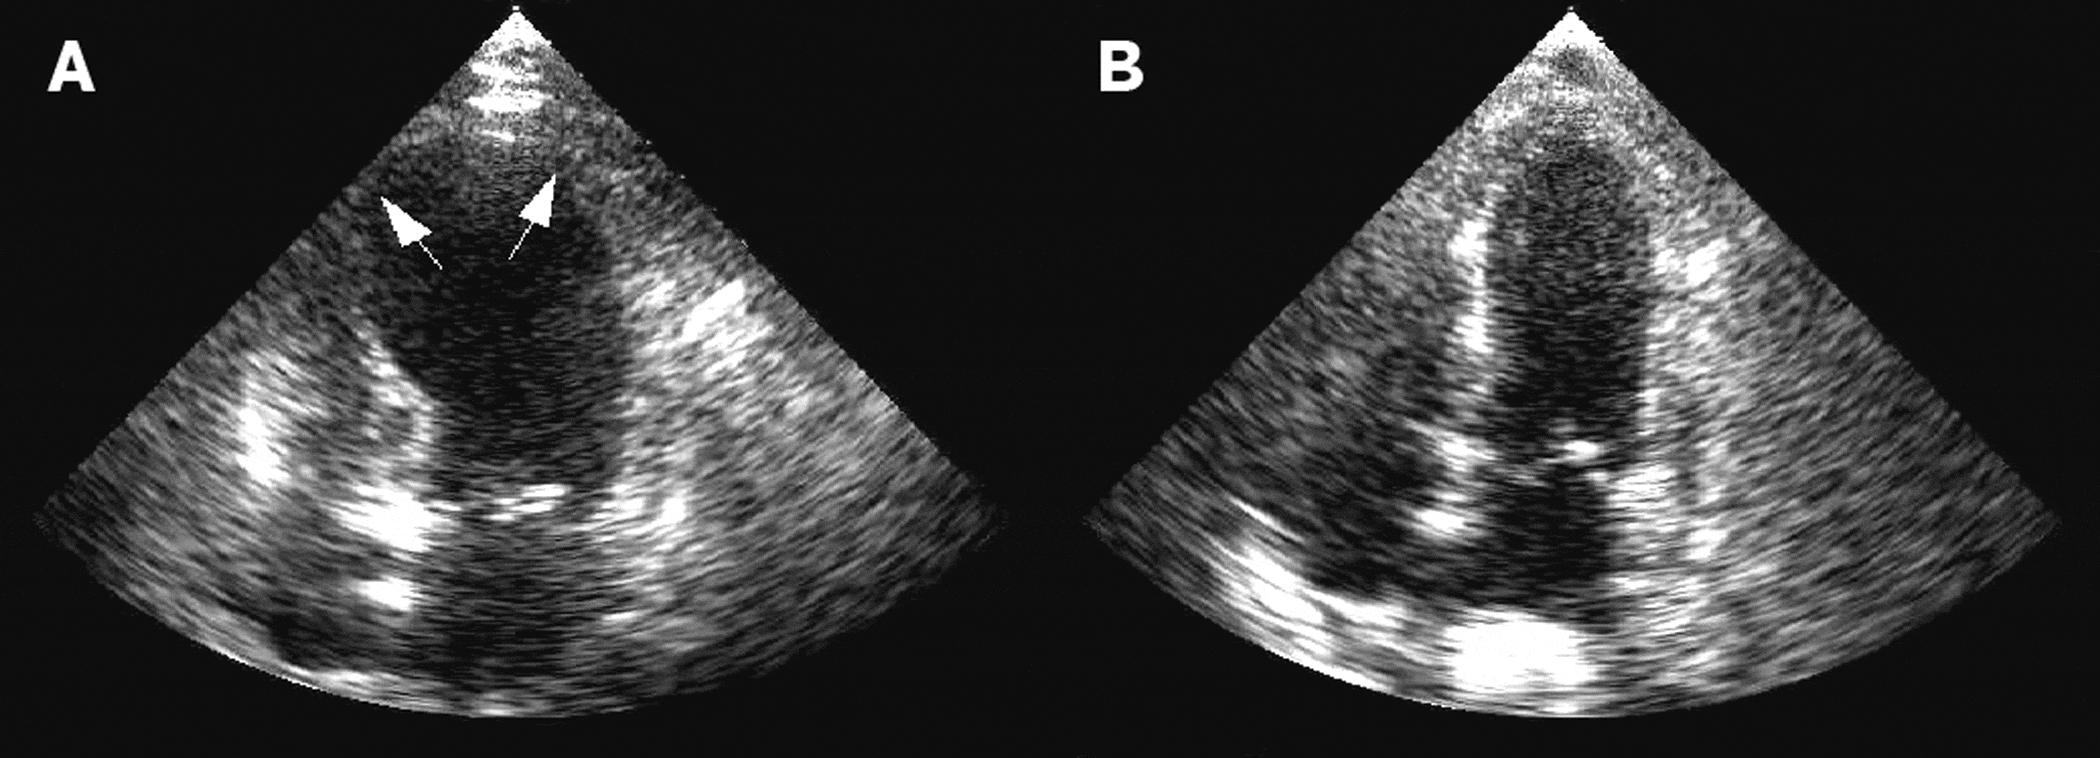

Dilated cardiomyopathy (A) Transthoracic echocardiogram in the Can You See Cardiomyopathy On Echo This test may be done if the images from an echocardiogram aren't enough to confirm cardiomyopathy. Cardiomyopathies include a variety of myocardial disorders that manifest with various structural and functional phenotypes with. In addition to history and physical examination, diagnosis of cardiomyopathy includes electrocardiography and echocardiography testing. There are several types of echo tests, including transthoracic and. There are six. Can You See Cardiomyopathy On Echo.